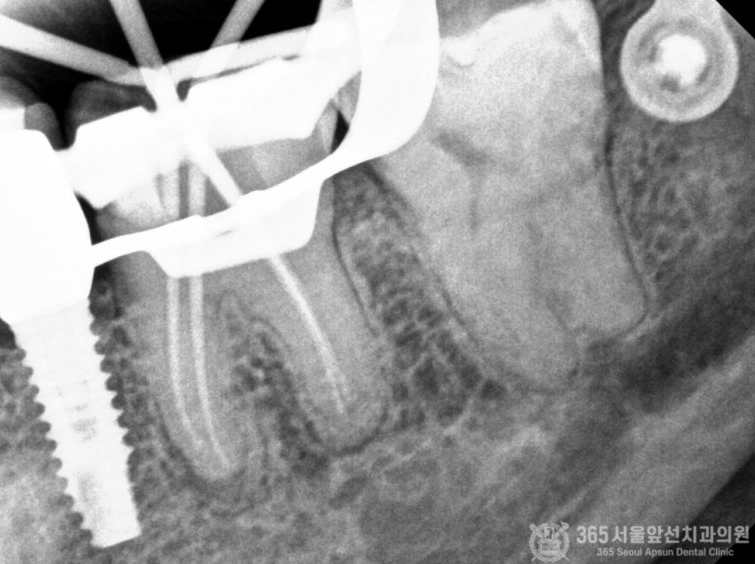

촬영일시 : 2024.06.18 러버댐을 걸고 치료원칙을 지켜서 신경치료를 진행하는 중입니다. 촬영일시 : 2024.06.18 신경치료가 마무리된 엑스레이 사진입니다 ㅎㅎ 서울대학교 출신 치과보존과 전문의 원장님의 깔끔하고 정확한 신경치료로 통증도 말끔하게 사라졌습니다.